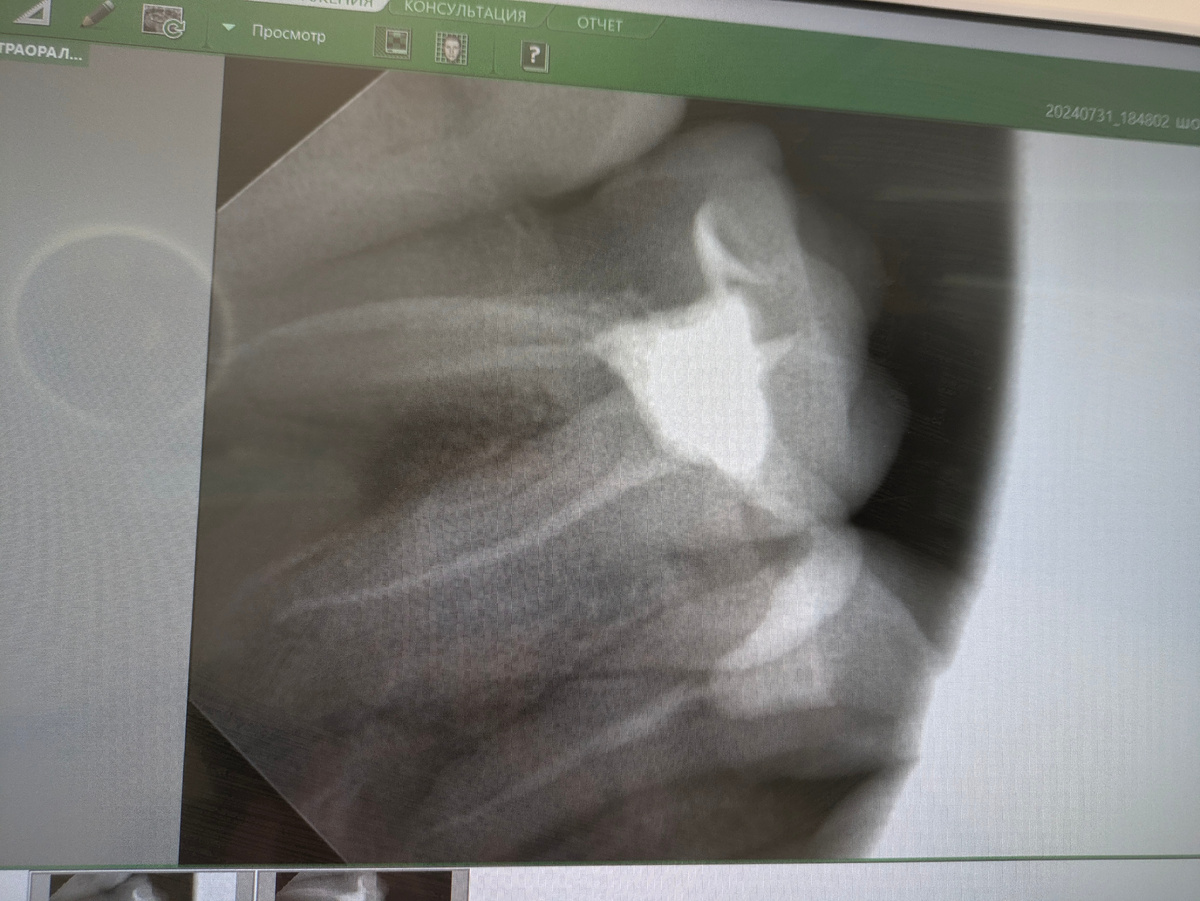

Снимок моего зуба из стоматологического кабинета

Меня приняли в шикарной клинике на осмотр. Я то думала, сейчас вскроют гнойник и все будет хорошо, но не тут-то было. Врач сделал снимок и сообщил, что у меня киста на корне зуба.